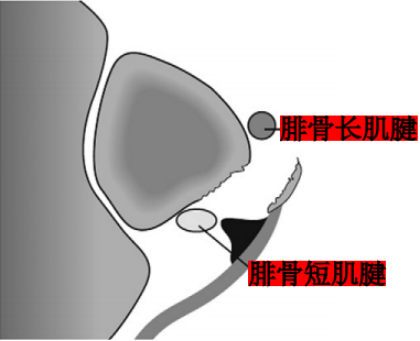

Ecket和Davis根据73例手术患者的术中观察发现并无腓骨上支持带的撕裂,他们将患者分为3型:

I型:最常见(51%),腓骨上支持带(SPR)和骨膜仍保持联系,骨膜从外踝上撕脱,腓骨肌腱滑向前方使骨膜和外踝分离。

Ⅱ型:(33%)纤维软骨脊连同腓骨上支持带(SPR)一起和外踝分离,腓骨肌腱向前脱位。

Ⅲ型:(16%)纤维软骨脊连同部分外踝骨质和腓骨上支持带(SPR)一起与外踝分离,肌腱脱位至骨折块下方。

IV型:Oden1987年在此基础上外,还有少见的第IV型,表现为腓骨上支持带(SPR)的完全撕脱或断裂,并且肌腱移位于支持带的外表面。

Raikin等学者提出将腓骨沟内腱鞘内半脱位不伴有腓骨上支持带损伤划为腓骨脱位的亚系。这些腱鞘内半脱位共有两型:

A型:腓骨肌腱无撕裂,肌腱暂时换位;

B型:腓骨短肌存在纵向撕裂,腓骨长肌腱自撕裂处半脱位。